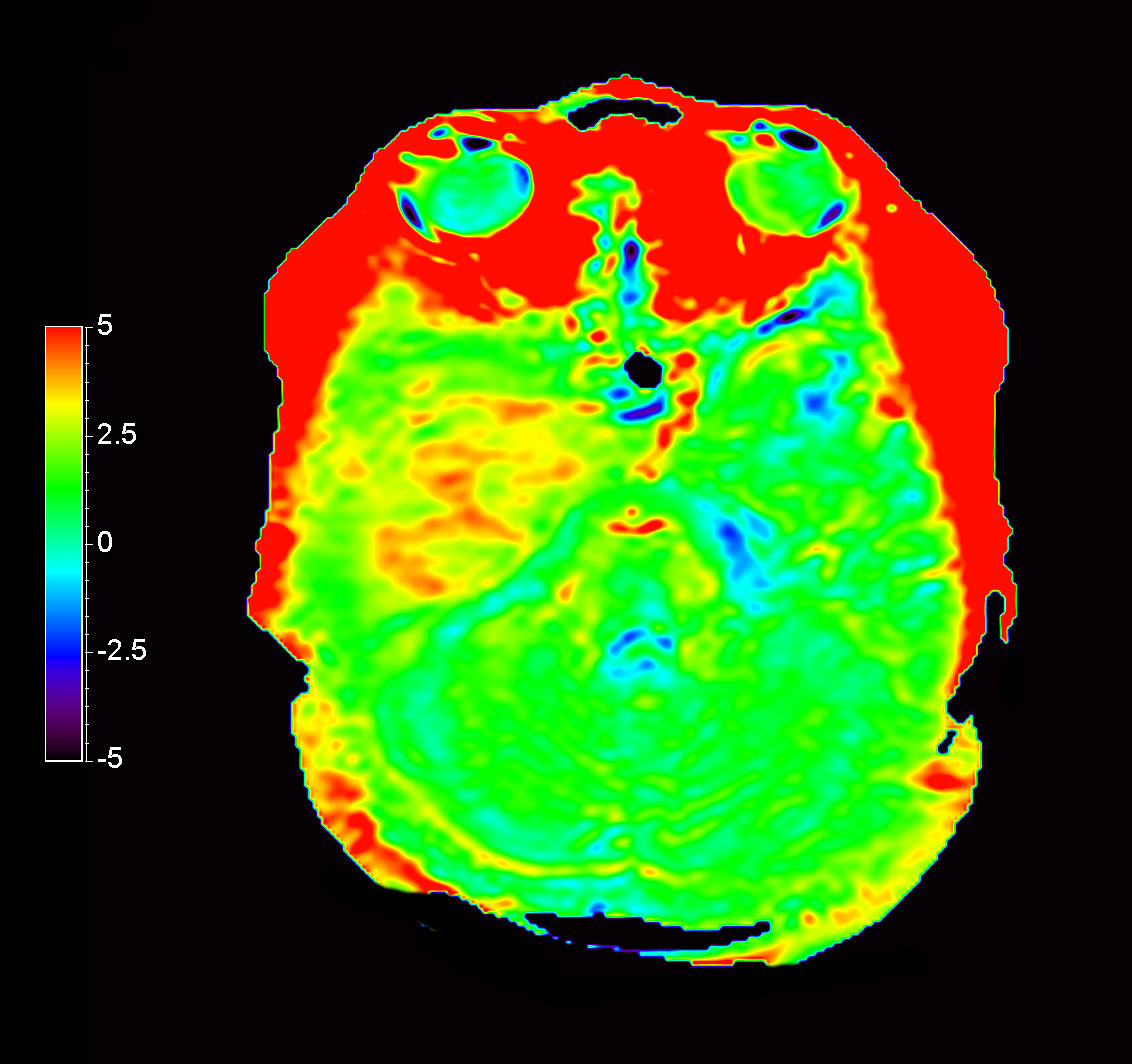

Axial 3D APT

-

Axial T2* Perfusion (Index)